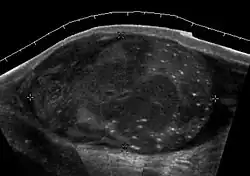

Primary leukemia of the testis is rare. However, due to the presence of blood-testis barrier, chemotherapeutic agents are unable to reach the testis, hence in boys with acute lymphoblastic leukemia, testicular involvement is reported in 5% to 10% of patients, with the majority found during clinical remission. The sonographic appearance of leukemia of the testis can be quite varied, as the tumors may be unilateral or bilateral, diffuse or focal, hypoechoic or hyperechoic. These findings are usually indistinguishable from that of the lymphoma [Fig. 9].

Fig. 9. Leukemia. Diffuse hypoechoic infiltrative lesions are seen involving the whole testis, indistinguishable from that of the lymphoma.